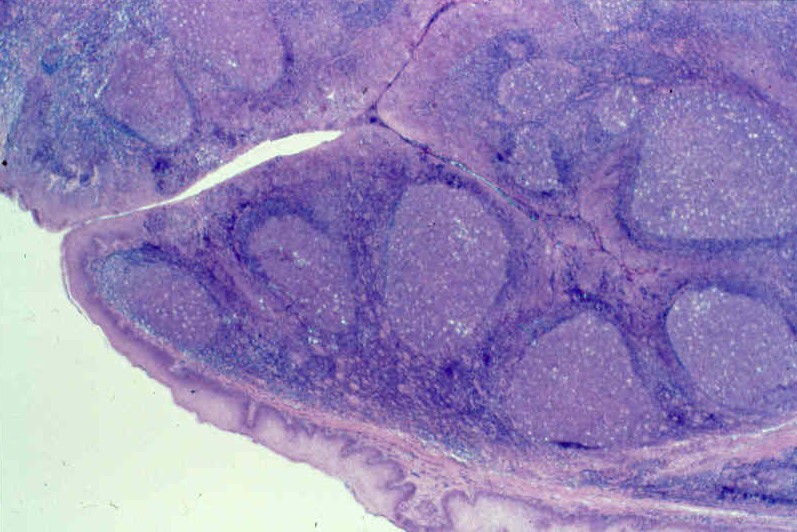

Ultrastructure of Tonsil

The tonsil is made up of a mass of lymphoid follicles within a fine connective tissue matrix. The lymphocytes are less closely packed in the centre of each nodule, otherwise known as the germinal centre, because multiplication of lymphocytes take place here. Medial surface of the tonsil, facing the oral cavity is characterised by 15 - 20 openings, irregularly spaced. These openings lead to deep, narrow and blind ended recess known as crypts. These crypts may penetrate nearly the whole of the tonsil. This feature distinguishes it from other lymphoid organs. The mucous membrane covering the medial surface of the tonsil is of non - keratinizing stratified type. It dips down to line the crypts.

These crypts may contain desquamted epithelial debris and cells. The largest of the crypts known as the crypta magna is present close to the superior pole of the tonsil. This is thought to represent the persistent part of the ventral portion of the second pharyngeal pouch.

Histology of Palatine Tonsil